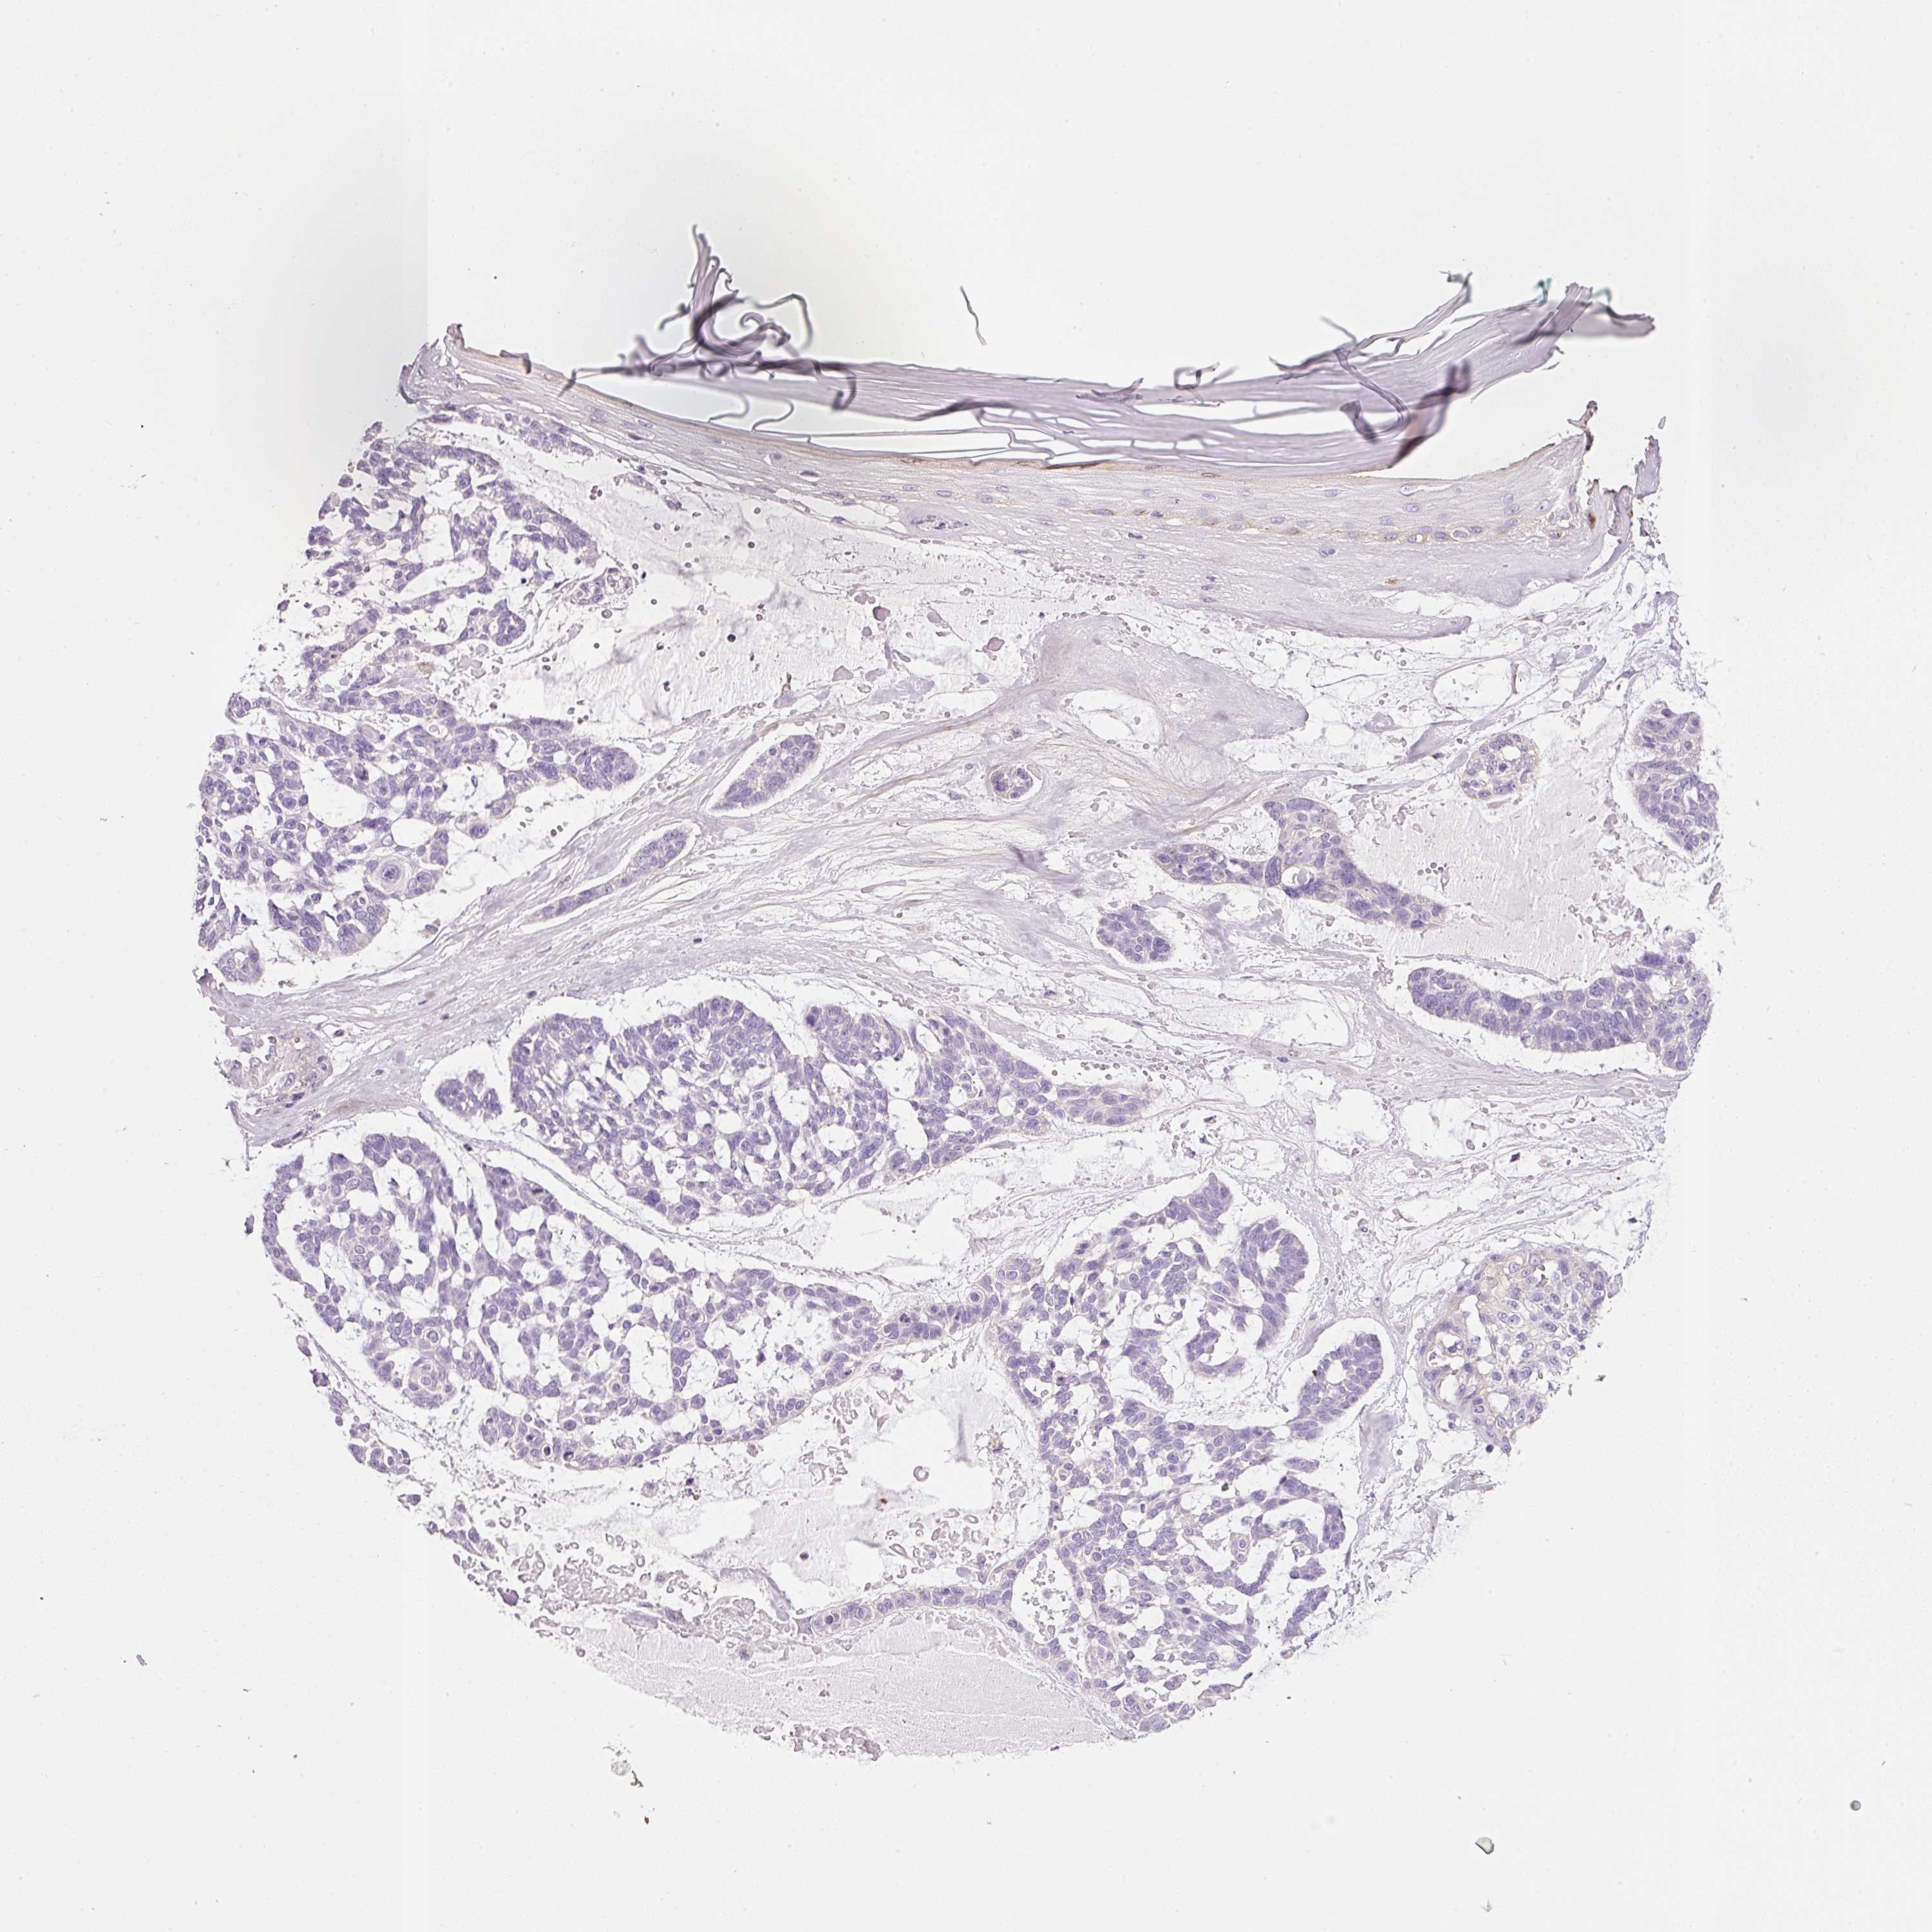

SKIN CANCER - Protein expressioni

A mouse-over function shows sample information and annotation data. Click on an image to view it in a full screen mode. Samples can be filtered based on level of antibody staining by selecting one or several of the following categories: high, medium, low and not detected. The assay and annotation is described here.

Antibody staining in the annotated cell types in the current human tissue is reported as not detected, low, medium, or high, based on conventional immunohistochemistry profiling in selected tissues. This score is based on the combination of the staining intensity and fraction of stained cells.

Each image is clickable and will lead to virtual microscopy that enables deeper exploration of all samples and also displays staining intensity scores, fraction scores and subcellular localization as well as patient and tissue information for each sample.

Basal cell carcinoma